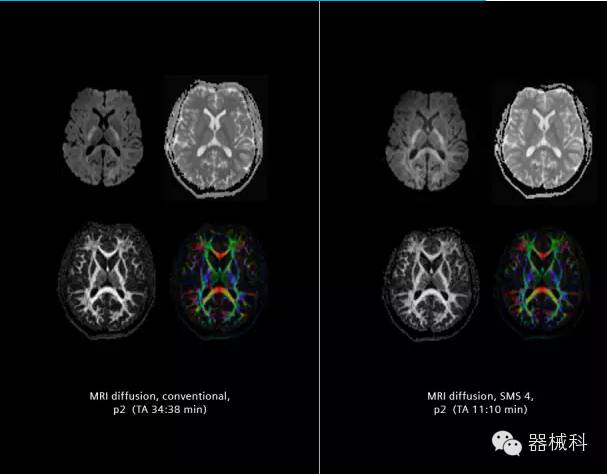

在2015年RSNA上,西門子隆重發(fā)布了Simultaneous Multi-slices 技術(shù)(即同時多層采集技術(shù),簡稱SMS),這是磁共振掃描技術(shù)中第一次引入“同時多層”的概念,此概念技術(shù)的發(fā)布,將對未來磁共振成像領(lǐng)域帶來巨大的變革!

SMS將高級成像技術(shù),尤其是神經(jīng)系統(tǒng)彌散成像時間縮短68%。

SMS技術(shù)可以將原本用于科研的高級成像技術(shù)轉(zhuǎn)化成臨床常規(guī)。

SMS可以有效提升高級功能成像精準(zhǔn)度

擁有了SMS“同時多層”采集技術(shù)之后,用戶可以在非常短的時間內(nèi)完成MR掃描,結(jié)合西門子靜音技術(shù),大大提高患者的舒適性,或在單位時間內(nèi)采集更多的數(shù)據(jù),也可以得到高精度、高準(zhǔn)確性、大數(shù)量的功能成像數(shù)據(jù),為臨床和科研提供強(qiáng)大的支持。專家認(rèn)為,SMS“同時多層”采集技術(shù)未來在 提高成像質(zhì)量、外科手術(shù)計劃、降低術(shù)后神經(jīng)功能缺陷、提高fMRI的時間采集效率、提高靜息態(tài)功能磁共振數(shù)據(jù)質(zhì)量等方面將帶來深遠(yuǎn)影響,希望該技術(shù)可以盡早面世,引領(lǐng)磁共振進(jìn)入多層時代!